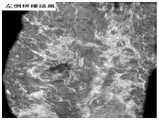

图8为被检查者A左侧乳房的C平面超声图像数据在检测深度为12.454mm,检测位置为AP(前后),Lateral(侧面)时的超声图像经过本发明算法拼接之后的结果。Fig. 8 shows the result of the ultrasonic image data of the left breast of the examinee A when the detection depth is 12.454mm, the detection position is AP (front and rear), and the ultrasonic image is spliced by the algorithm of the present invention.

图11为被检查者A右侧乳房的C平面超声图像数据在检测深度为12.454mm,检测位置为AP(前后),Lateral(侧面)时的超声图像经本发明算法拼接之后的结果。11 is the result of the ultrasonic image data of the C-plane of the right breast of the examinee A when the detection depth is 12.454mm, the detection position is AP (front and rear), and the Lateral (side) is spliced by the algorithm of the present invention.

图14为被检查者B右侧乳房的C平面超声图像数据在检测深度为9.123mm检测位置为AP(前后),Lateral(侧面),Medial(中间)时的超声图像经本发明算法拼接之后的结果。Figure 14 is the ultrasonic image data of the C plane of the right breast of the examinee B when the detection depth is 9.123mm and the detection positions are AP (front and rear), Lateral (side), and Medial (middle) after the ultrasonic images are spliced by the algorithm of the present invention result.

S3:全景图拼接。本步骤的实验拼接结果可由图8,图11和图14可见。S3: Panorama stitching. The experimental splicing results of this step can be seen in Figure 8, Figure 11 and Figure 14.

(3)图片融合。实验中首先分别提取三例图像数据遮罩重叠区,准备亮度拉伸参数,提取图片遮罩左边坐标,利用find函数分别找到进行拼接的两张图片的非零位置最小坐标,通过比较两边最小坐标构造图片左右权重遮罩的坐标矩阵,权重遮罩构造完成之后用vision.AlphaBlender将图像重叠起来,分别对图片采用step函数得到融合之前的准备图像,注意将其中的矩阵类型转换为unit8之后,进行最终的图像相加融合,即拼接全景图完成。经过本算法实验,得出被检查者A的左侧乳房拼接结果为图8,被检查者A右边乳房拼接结果为图11,被检查者B右侧乳房拼接结果为图14。(3) Image fusion. In the experiment, firstly extract three cases of image data mask overlap area, prepare brightness stretching parameters, extract the left coordinate of the image mask, use the find function to find the minimum coordinates of the non-zero position of the two images to be spliced, and compare the minimum coordinates on both sides by comparing the minimum coordinates of the two images. Construct the coordinate matrix of the left and right weight masks of the picture. After the weight mask is constructed, use vision.AlphaBlender to overlap the images, and use the step function on the pictures to obtain the prepared images before fusion. After converting the matrix type to unit8, proceed to The final images are added and fused, that is, the stitched panorama is completed. After the experiment of this algorithm, the result of splicing the left breast of examinee A is shown in Fig. 8, the splicing result of the right breast of examinee A is Fig. 11, and the splicing result of the right breast of examinee B is Fig. 14.